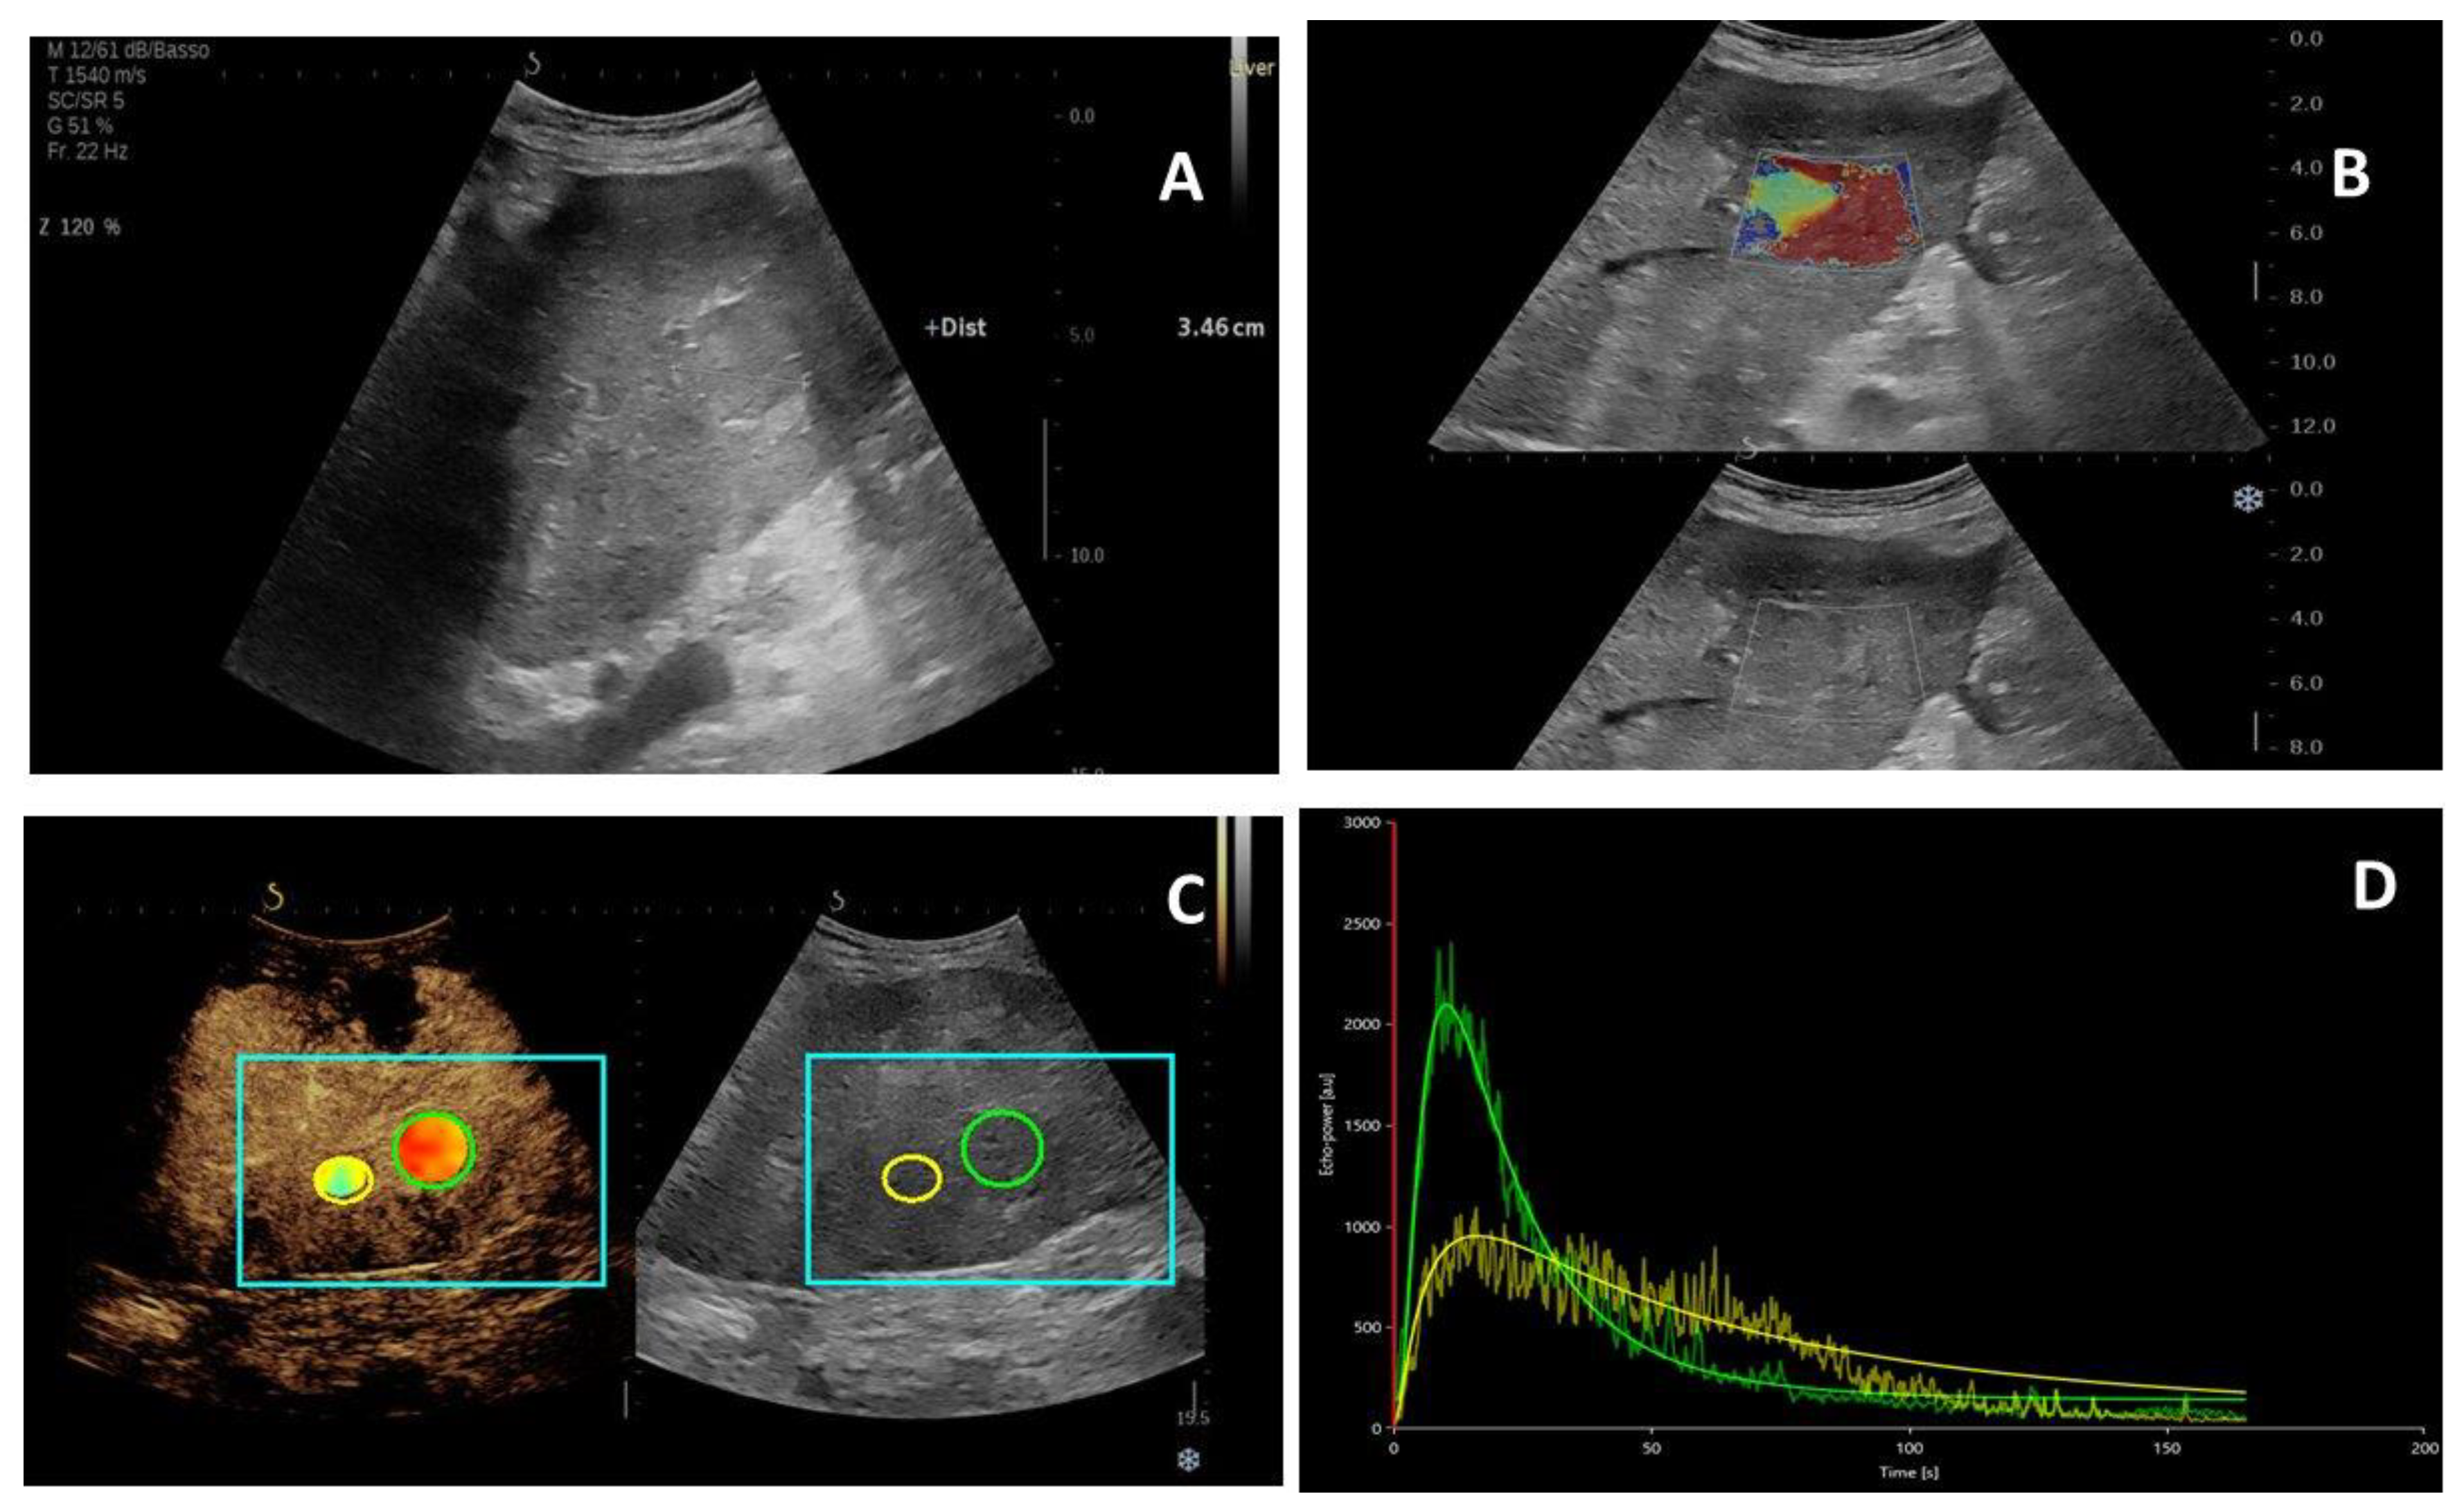

2.1. Patients Clinical Data

2.2. US Imaging Characteristics

4.2. Study Protocol

4.3. Multiparametric US Examination

4.4. Image Analysis